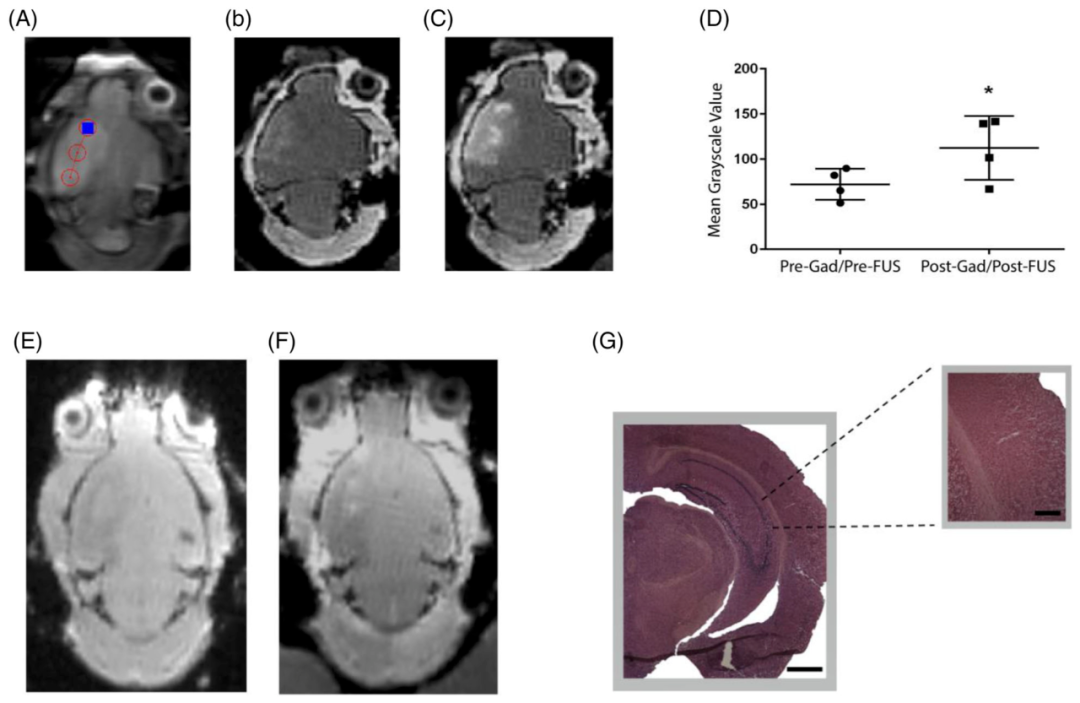

图3. FUS不会引起出缺血脑组织的出血损伤

A-C. tpMCAo后诱导的急性缺血性卒中小鼠用Gd-DTPA增强MRI成像,暴露于FUS,并使用Gd-DTPA标注成像。A. T2序列显示卒中区域和3个选定的FUS目标(红色圆圈)。B. T1加权序列证实在FUS前缺血性卒中区中的Gd-DTPA增强。C. T1加权序列显示FUS后在目标区域有Gd-DTPA显著增强。D.显示在FUS后,Gd-DTPA增强磁共振成像像素灰度显著增加。这些数据表明,暴露在FUS下的缺血脑组织中存在大量的血脑屏障开放。E.FUS超声检查前和F.检查后的GRE序列,提示未检测到出血性并发症。G.组织学染色证实无微出血。对暴露脑区进行H&E染色连续切片,均未发现微出血。